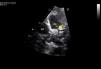

Latente do sexo feminino, com oito meses de idade, com história de má progressão ponderal a partir dos quatro meses e duas pneumonias, aos cinco e oito meses. Ao exame objetivo apresentava polipneia, S3 e sopro holossistólico grau III/VI no ápex com irradiação para a axila. Na radiografia de tórax observou‐se cardiomegalia, com índice cardiotorácico de 60%. O eletrocardiograma mostrou ondas Q>3mm em DI, aVL e V7 e inversão da onda T de V5‐V7, padrão sugestivo de enfarte do miocárdio. O ecocardiograma transtorácico revelou dilatação e disfunção global do ventrículo esquerdo (VE), com diâmetro diastólico (VEdd) 46mm (Z‐Score+12,44), fração de encurtamento (FEnc) 16% e fração de ejeção (FEj) biplano 25,4%, com regurgitação mitral grave por má coaptação dos folhetos. A artéria coronária esquerda (CE) tinha origem no tronco da artéria pulmonar (ALCAPA) (Figuras 1 e 2). Foi referenciada para cirurgia com base exclusivamente na informação destes exames. A correção cirúrgica consistiu na reimplantação da CE na aorta (Figuras 3 e 4). A cirurgia e o pós‐operatório decorreram sem complicações. Teve alta oito dias depois, apresentando redução das dimensões do VE e melhoria significativa da função sistólica global (VEdd 33mm, Z‐Score+5,22, FEnc 23% e FEj biplano 41,3%). Aos três meses após cirurgia a criança está clinicamente bem e com normalização da função ventricular.